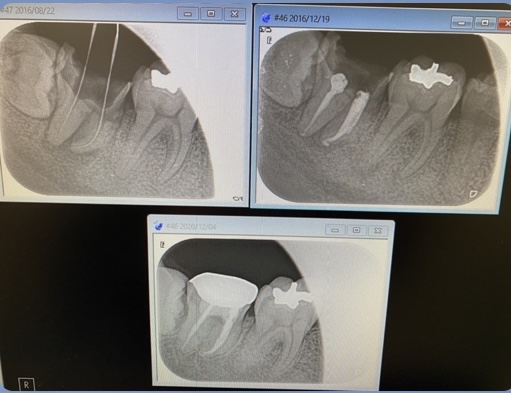

根尖病巣

本日4年振りにお見えになった患者さん

右下7番の大臼歯が大きなう蝕で歯冠部から歯根付け根まで崩壊、また根尖には感染が広がり歯槽骨を溶かす膿の影響がレントゲン画像の透化像として確認出来ました、、

抜歯が無難な症例ではありますが、患者さんの意向もあり、保存治療に!

根管治療を地道にコツコツと拡大、根管内を殺菌消毒すること4ヶ月、、前術のNTオブチュレーションテクニックにて根管充填し被せ物をしました。(すべて保険治療です)

4年後に来院された同患者さんの同部位のレントゲン画像‼︎

オーバー気味の純度100%のオブチュレーションガッタパーチャーも綺麗にした組織の貪食細胞が一掃してくれて消失‼︎‼︎ 人間の体って健全な状態に戻すと治癒力で要らない物は排出してくれるんです(生命の力ですね♪)